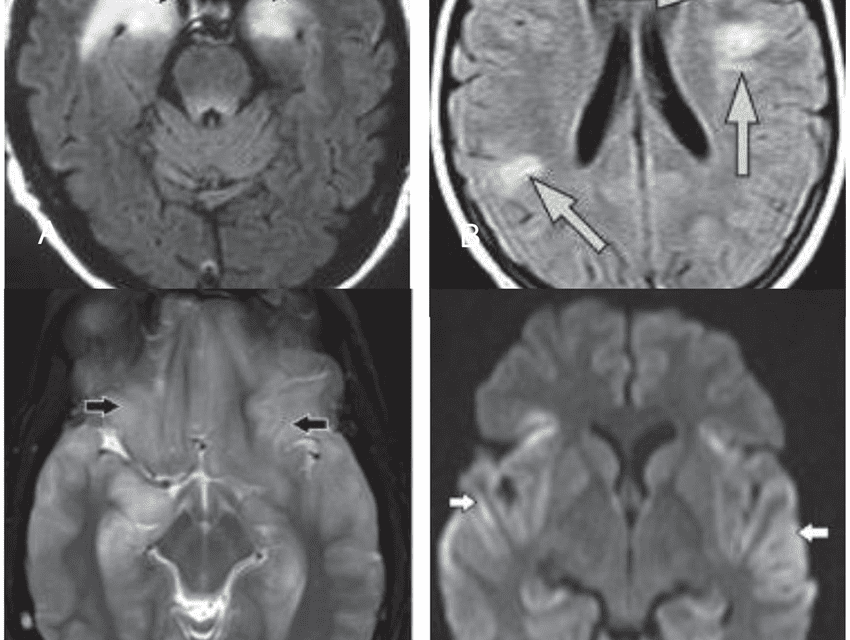

Limbic encephalitis is a type of inflammation of the brain involving the limbic system. The limbic system is the area of the brain that controls our emotions, like love, anger, jealousy and sadness. The limbic system includes the hippocampus, hypothalamus and thalamus as well as the amygdala.

Though there are multiple causes of limbic encephalitis most types fall into one of two main categories; infectious limbic encephalitis or autoimmune limbic encephalitis. Though any infection involving the brain has the potential to cause an inflammation of the brain viral infections appear to specifically target the limbic areas of the brain. The most common viral infection associated with limbic encephalitis is the herpes simplex virus. Limbic encephalitis can also be caused by an abnormal autoimmune response. It is the responsibility of our immune system to identify and eliminate infections, however, sometimes the antibodies produced by our immune system react to proteins in our bodies instead of an infection causing autoimmune diseases. Autoimmune limbic encephalitis is classified either as paraneoplastic limbic encephalitis or PLE, or non-paraneoplastic limbic encephalitis or NPLE. PLE usually occurs in people diagnosed with certain types of cancer. The most common form of cancer that is usually involved is small cell lung cancer, however, PLE also occurs in people with other types of cancer including breast cancer, ovarian cancer and testicular cancer as well as others. On the other hand, NPLE has only been recognized in recent years. In people with NPLE there is no evidence of tumors or cancer. Instead NPLE is believed to be caused by certain antibodies in the blood that targets the limbic areas of the brain, especially the hippocampus.